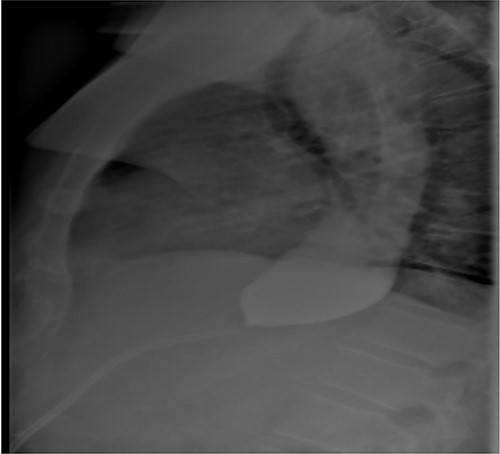

Three months after band removal, the patient reported complete resolution of his symptoms. Repeat gastroscopy demonstrated oesophageal mucosal healing and no residual hiatal hernia. TTE showed that left atrium was moderately enlarged (but to a lesser extent compared to previous study) and normal left and right ventricular systolic function and dimensions with estimated left ventricular ejection fraction of 60%. Furthermore, the post-operative Barium swallow study (Fig. 4) demonstrated a 6.7-cm oesophageal dilatation and dysmotility. There was no significant delay in passage of barium into a non-distended stomach. Since band removal his weight had increased by 17 kg (112.8 kg, BMI: 36.4). Further discussions with the patient led to laparoscopic sleeve gastrectomy a month later (Fig. 5).

Barium contrast swallow study demonstrating ongoing oesophageal dilatation, however, free passage of contrast into the stomach.